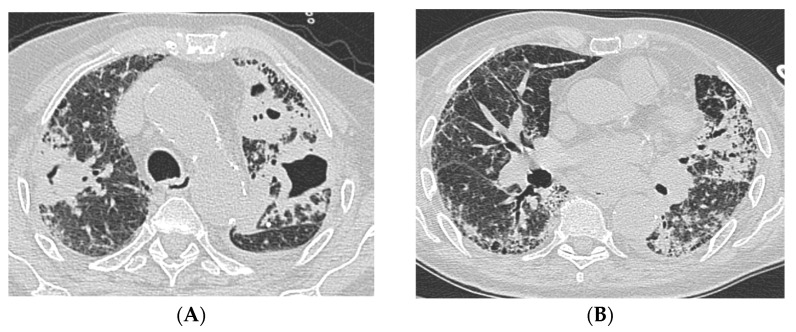

Background: Interstitial lung diseases (ILDs) are a heterogeneous group of conditions that can cause fibrosis of the lung interstitium, resulting in respiratory failure and death. Patients with an ILD, particularly idiopathic pulmonary fibrosis (IPF) or connective tissue disease-associated ILDs (CTD-ILDs), are prone to develop chronic pulmonary infections such as tuberculosis (TB) and non-tuberculous mycobacterial pulmonary disease (NTM-PD).

Methods: This case series examines the management of three ILD patients with a usual interstitial pneumonia (UIP) pattern and concomitant NTM-PD or TB at National Institute for Infectious Diseases "Lazzaro Spallanzani" in Rome, Italy, over three years (2019-2022).

Results and conclusions: Multi-disciplinary discussion (MDD) was crucial to define the therapeutic approach due to the increased risk of side effects and drug interactions. Our work underscored how a comprehensive diagnostic evaluation, enriched by MDD, is useful for optimizing the management and reducing drug-related adverse effects and interactions in ILD patients with cavitary lesions.